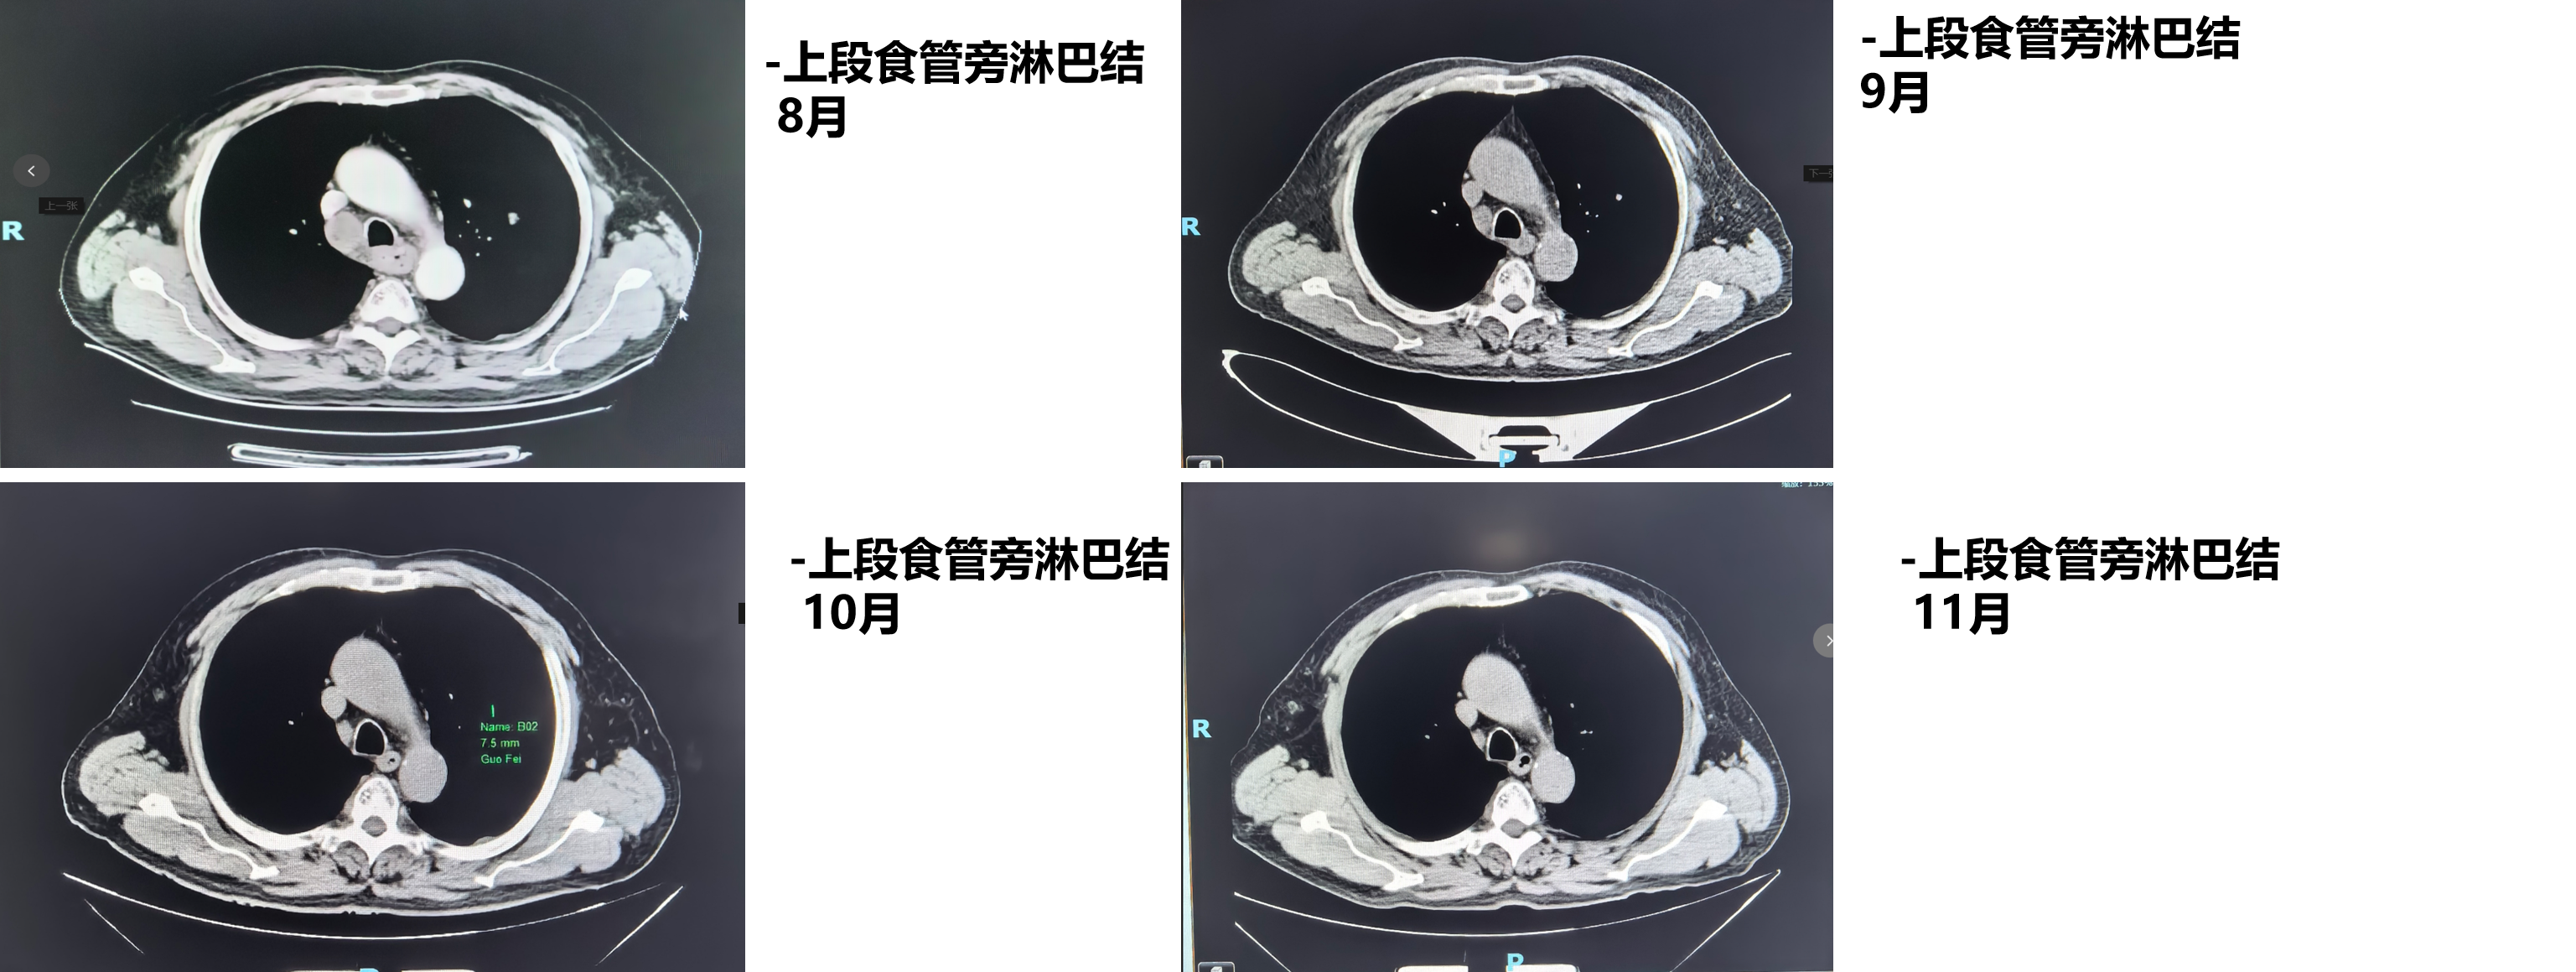

1周期后(2025年9月)复查CT:食管病变、纵隔淋巴结较前减小,双肺转移结节较前部分减小。1周期即显现疗效。

4周期后(2025年11月)复查CT:与2025-10-17日图像对比,食管癌治疗后改变,同前相仿;纵隔淋巴结治疗后改变,较前减小;双肺多发小结节,考虑转移瘤治疗后改变,部分较前略减小。

疗效评估:达到部分缓解(PR)

本例患者PD-L1 CPS评分为3分,属于CheckMate 648研究中获益更为显著的PD-L1阳性人群。经过4个周期纳武利尤单抗联合化疗后,影像学复查显示原发灶及所有转移病灶均明显缩小,疗效评估达PR,与研究中PD-L1阳性患者高达53%的ORR相符。